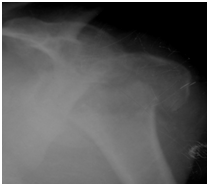

Figure 3 6 Weeks post operative-Prior to fixator removal.

Figure 4 6 months postoperative film-The humeral head appears contained in glenoid and the patient had reasonable shoulder function. The head of humerus did not appear avascular at 6 months.

Figure 5 14 months postoperative-The humeral head appeared contained with post traumatic arthritis due to avascular necrosis. Active abduction was about 90 degrees at shoulder.